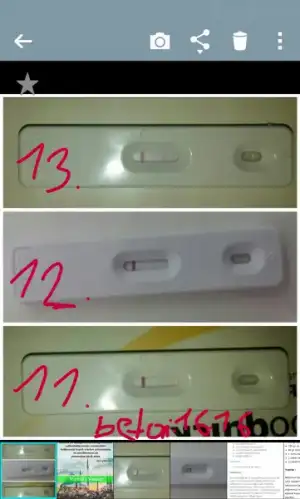

Canim benimde 6 mayis adet günüm test yaptim test bozuk çıktı bugun tekrar deniyecegim inslh bende gectigimiz ay dr gittim hormonlra bakildi esimin sperm bakildi hersey normal görünüyor 10. Ayimiz olacak bu ben boyle zor hamile kalinacagini bilseydim oglumdan sonra hic korunmazdim yasim oldu 37 rabbim yüzümüzü guldurur inslhEvet canim 17 ay oldu hala ayni malesef .hsg cektrdim bu 2. Adetim olcak 4 gun var.testler negatf.adet belirtilerim var bu ayda yok yanj.haftaya prof a gidicem belki asilama deneirz ramazan oncesi bakalim.sende durumlar ne